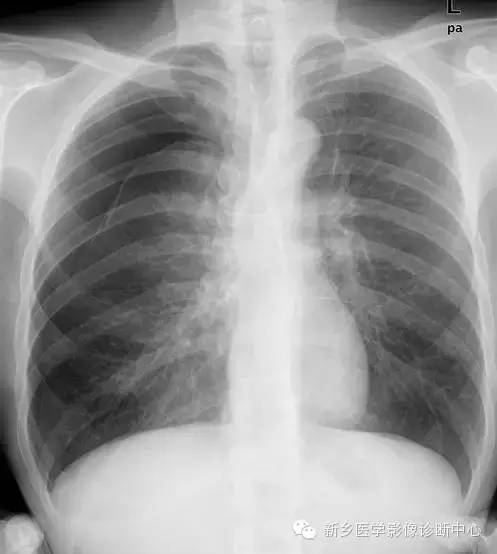

气胸时肺组织被压缩的程度,对于临床的治疗有着重要意义(如闭合性气胸,肺压缩<20%者,单纯卧床休闲气胸即可自行吸收),所以对气胸程度进行判定是必要的。

一般将气胸分为四度,有多方法计算。

二、考虑气体分布特点、结合肺萎陷程度将气胸分为四度。

1度:新月形气体位于肺尖和上肺野外带,肺尖部发线不低于锁骨上线。

2度:发线影位于肺野中外1/3处。肺尖低于锁骨下缘。

3度:无肺纹区达1/3至2/3部分。

4度:超过3度,无肺纹区超过肺野2/3以上。

三、Kircher方法:

在气胸侧,以横突外缘至胸壁内缘为基准范围(为整个一侧肺野),

• 当肺野外侧受压至上述范围之1/4时,肺组织大约受压35%;

• 当受压至1/3时,肺组织受压50%;当受压1/2时,肺组织受压65%;

• 当受压至2/3时,肺组织受压80%;

• 而当肺组织全部被压缩至肺门,呈软组织密度时,肺组织受压约为95%.

• 如果少量气胸仅限于上肺野,则将肺野外带自上而下分为三等份,然后以上述方法中受压1/4时的35%均分,大约为10%-15%.